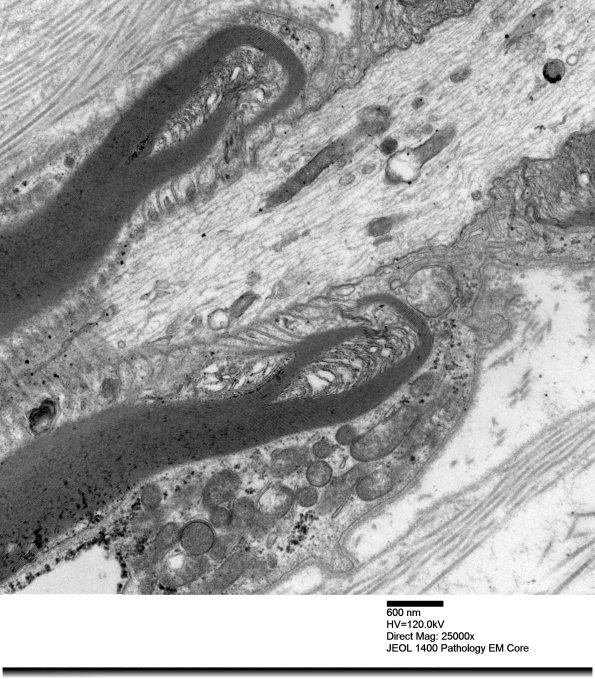

Washington University Experience | PERIPHERAL NEUROPATHY | 3 NORMAL MYELIN & SCHWANN CELLS | 2 Node of Ranvier | 12A2 Node Ranvier (Case 2 longitudinal 012 - Copy

12A2,3 Note the prominent microvilli (arrow, 12A3). (electron micrographs)